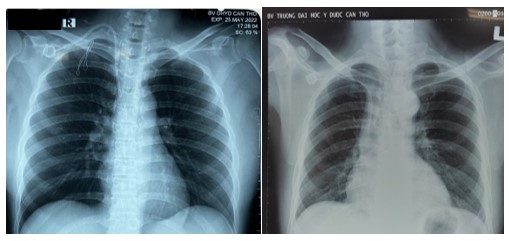

Hình 4. Hình ảnh X. quang sau đặt buồng tiêm